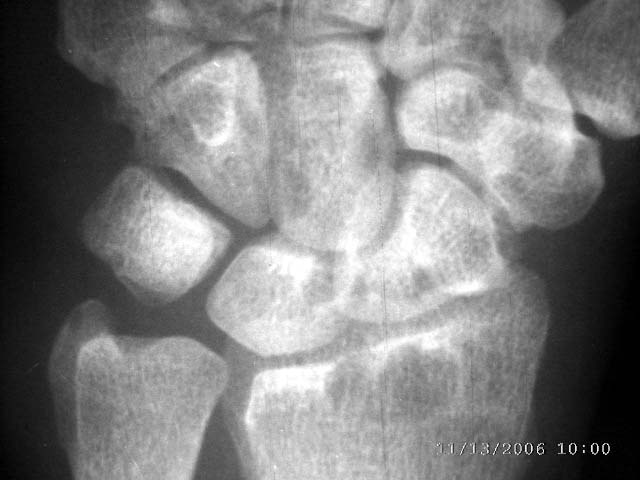

女45,右腕部夜间痛,晨僵感,局部皮温高,尺骨茎宊处轻度软组织肿胀2年余。自小感觉右手温觉和痛觉差。

右桡骨下端、舟骨,月骨,三角骨,头状骨,尺骨茎突均可见囊状低密度影,尺侧软组织似稍肿胀。患者虽然为女45,右腕部夜间痛,晨僵感,局部皮温高,尺骨茎宊处轻度软组织肿胀2年余。但类风湿似乎不象,我认为应考虑结核。

右桡骨下端、舟骨,月骨,三角骨,头状骨,尺骨茎突均可见囊状低密度影,尺侧软组织似稍肿胀。患者虽然为女45,右腕部夜间痛,晨僵感,局部皮温高,尺骨茎宊处轻度软组织肿胀2年余。我认为应考虑结核。(依据可见吻状破坏),自小感觉右手温觉和痛觉差,症状像神经性骨关节病,但影像不像。